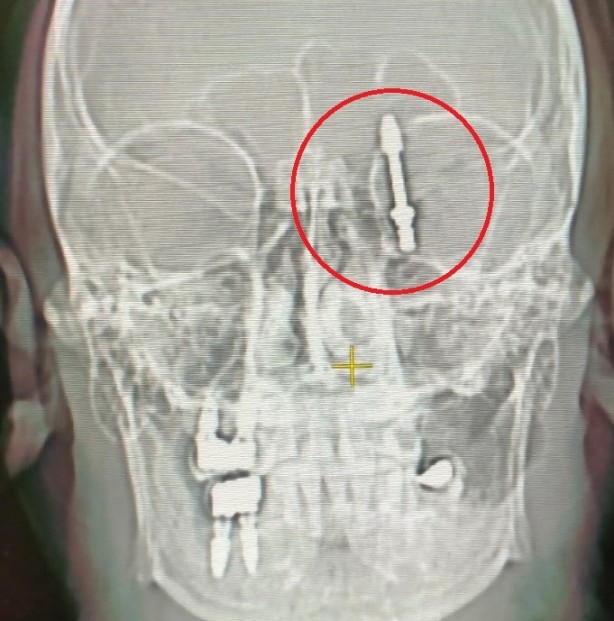

Bursa'da bir vatandaşın sızı yapan dişlerinin tedavisi için gittiği özel bir klinikte implant tedavisi başlatıldı. Doktor çeneye yerleştirecek vidayı zorlayınca vida çene kemiğini delip hastanın beynine saplandı. Hastaneye kaldırılan vatandaş saatler süren ameliyat sonrası hayata tekrar döndü.

İddiaya göre, implantı çeneye yerleştirmek isteyen doktorun yanlış müdahalesi sonrası vida, Yılmaz'ın çene kemiğini delip kafatasına saplandı. Acı içinde kalan Yılmaz'ın yaşadığı baygınlık sonrası film çeken Doktor A.D., vidanın kafatasında olduğunu görünce hemen kendi aracıyla Yılmaz'ı bir hastaneye bıraktı.

Hastanede çekilen tomografi sonrası gözlerine inanamayan doktorlar, 2 çocuk babası adamı hemen ameliyata aldılar. Saatlerce süren operasyon sonrası hayata tekrar dönen Yılmaz, günlerce taburcu olmayı bekledi. Sağlığına dönen Yılmaz, kendisine yanlış müdahale yapan diş hekimini aradığında ise ikinci bir şoku yaşadı. Yaptığı ödemenin iadesini isteyen Yılmaz'a doktor tarafından ret cevabı gelince Yılmaz, yargının yolunu tuttu.

Kendisini uyarmasına rağmen dinlemediğini ifade eden Yılmaz, "Daha sonra dişlerimi çekip, aynı gün implant uygulaması yaparken, işlemde kullandığı cihazın bozuk olduğunu sekreterine söyledi. Bu kez de işlemi eliyle yapmaya başladı. Vidayı yerleştirmeye çalışırken, aşırı yüklendiğini fark ettim. Bunu kendisine söyledim, kemik sesi geldiğini ifade ettim. Fakat bu kez de bana bunun normal olduğunu söyledi. Ama vidayı zorlarken, vida çene kemiğimi delip göz duvarının arkasından beyin omurilik sıvısının olduğu bölgeye saplandı. Ben acıdan dolayı bağırınca röntgen çektirdi" dedi

Doktorun kendisini hastaneye bırakıp kaçtığını iddia eden Yılmaz, "Durumun ciddiyetini anlayınca beni Uludağ Üniversitesi Hastanesinin Acil bölümüne getirip gitti. Burada yapılan inceleme sonrası vidanın beyin omurilik sıvısının olduğu yere saplandığı görüldü. Daha sonra uzman hekimler bir araya gelip, ameliyat için karar aldılar. Ameliyat öncesi bana hayatımı kaybedebileceğimi söylediler. Ben artık çocuklarımla helalleşip vedalaştım. Çok şükür ameliyattan sağ salim çıktım.

Öte yandan, kendisine yönelik suçlamalara daire konuşan doktor A.D., "Tıbbi bir komplikasyondan dolayı böyle bir olay gerçekleşti. Kendisi benimle ilgili bu konuda yasal yollara başvuru yaptı, fakat benim böyle bir tavrım olmadı" ifadelerini kullandı. Öte yandan Yılmaz'ı sağlığına kavuşturan doktorların başarılı ameliyatı, Amerika'da literatüre girip dergilere konu oldu.